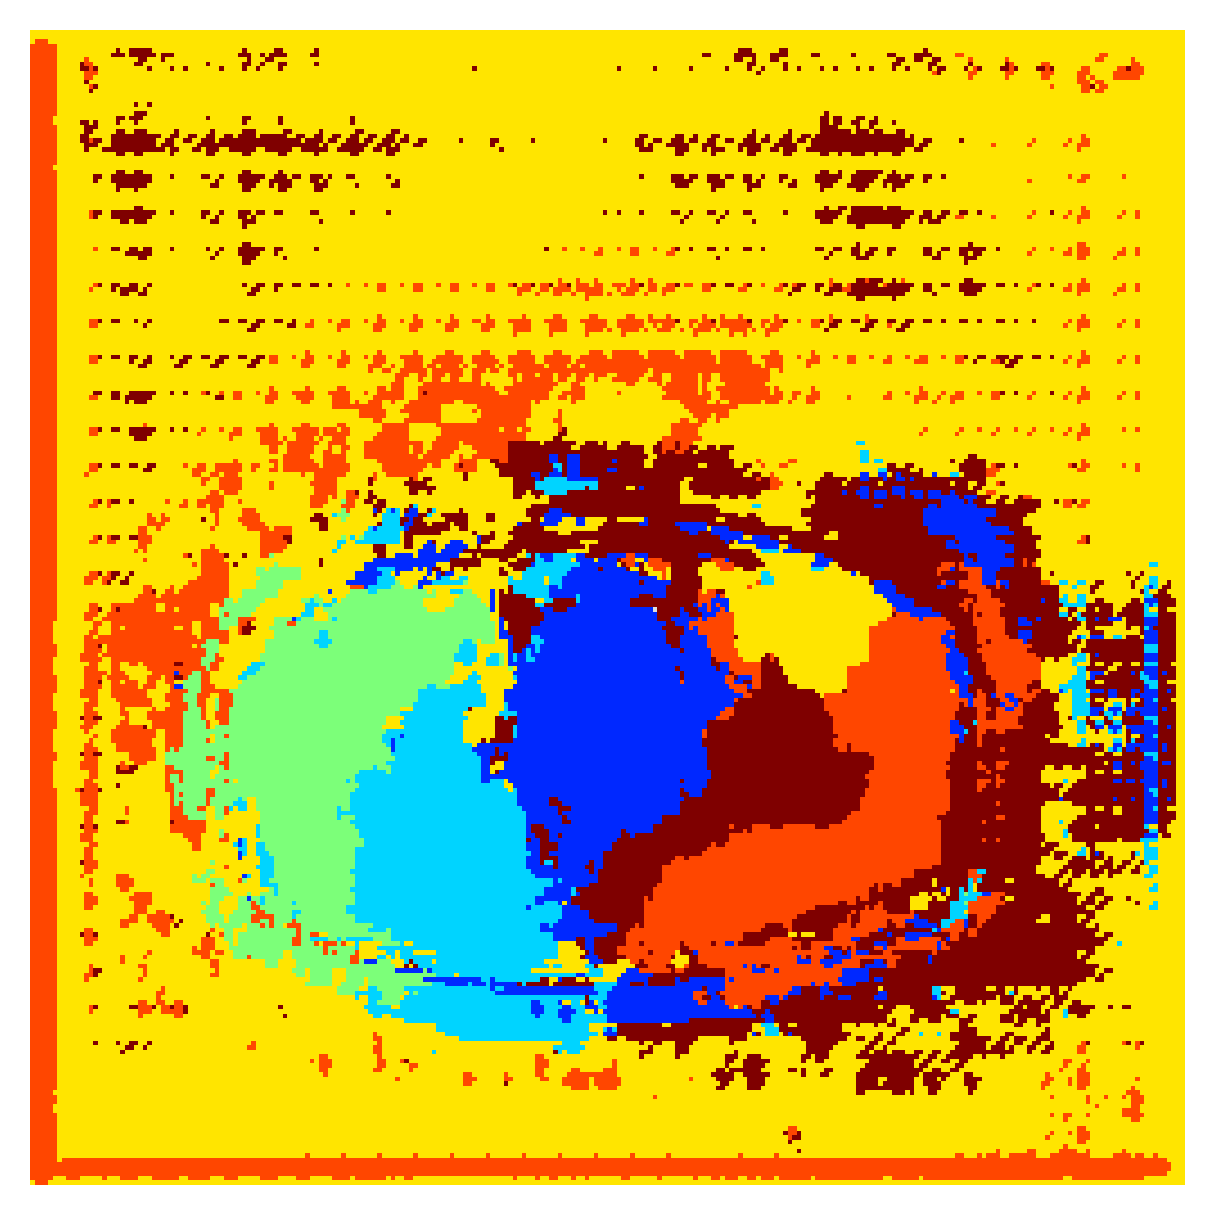

5.2.1 Qualitative comparison

In Figure 11 and 12 we show the same random slices in cases of calculating the boundary loss on 2D- and 3D-based distances, respectively. Comparing the two figures again indicates that the intensity-aware distances offer most improvement when calculated in 3D over 2D. The exception here is the MBD, which seems to even slightly degrade for most classes.